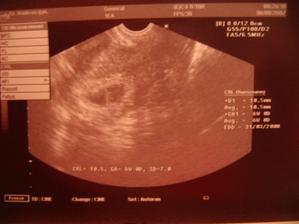

...abyste byli v obraze, že nejsem z Kutné Hory koudelníkův syn, tak máma tady vymejšlí můj rodokmen http://www.myheritage.cz/FP/family-tree.php?s=4... Dnes (2.11.2008) kdy mamka s taťkou jsou spolu přesně 5 let, a kdy přesně před rokem mě viděli na 3D ultrazvuku, jsem byl poprvé plavat v bazénu. Máma se toho bála-aby třeba neuklouzla a tak, ale moc jí to bavilo a mě taky....voda bude můj kamarád. Nejdřív jsem vypadal, že mě to nějak nebere-ruku v puse, pohoda...ale pak mě lili vodu na hlavu a to byla legrace.....Takže každou neděli teď budu plavčík na Zlatejch pískách:o)K 18.11.2008 mám 8,28kg a 75 cm.Včera (16.12.2008 kolem 17 hodiny) se stala dlouho očekávaná chvíle-začal jsem si stoupat na zadní. Nikdo mě k tomu nenutil, chytl jsem se tyček v ohrádce a už jsem to zkoušel...takže máma a táta byli přitom a byli tomu moc rádi. Dnes mám 9 měsíců a zítra mě dá mamka pozlatit, protože tak hodný miminko si prý nic jiného nezaslouží. Jinak už podávám věci do ruky-aniž bych to měl umět...prostě jsme to zkusili a šlo to-od té doby podám všechno....A jaké změny nás potkali za ten měsíc? v 10 měsících vážím přesně 9kg a měřím skoro 76cm. Od 15.1.2009 začínám se pouštět ohrádky když stojím-jo stojím krásně už měsíc a od 17.1.2009 vstanu sám uprostřed ohrádky-bez držení!!!Včera )18.1.2009 mě naši přestěhovali do vlastního pokojíčku. Noc byla jako každá jiná-spal jsem celou noc a ráno jsem vesele žvatlal v postýlce....takže už bydlím sám. Jsem velkej na to dost, ne?KONEČNĚ! v pondělí 2.2.2009 máma našla první zubisko!!!!!!!!jednička v pravo dole.ZPRÁVA JAK HROM!14.2.2009 jsem se pokusil o první kroky-k mamince. Pustil jsem se ohrádky a ťap ťap k ní. Táta to natočil na kameru. Měli velkou radost. Musím se naučit chodit---maminka mě pak s pupíkem nebude moct tolik nosit:o).Dnes 19.2.2009 mi mamka našla druhý zubisko! Už se pokouším přecházet přes celou ohrádku---nejistě, ale s nadšením!Už chodím víc a víc jistě. Ukazuju na mámu a na tátu.Už se nechávám vodit za ruce po bytě. Včera 15.3.2009 jsem přišel na to, jak skládat pyramidu, včera mi dala mamka chleba se žervé-dobrý. Dnes 16.3.2009 jsem byl poprvé u paní zubařky. Dala nám kartáček a obrázek. Byl jsem opět hodný kluk. Dnes 19.3.2009 jsem byl na kontrole v prvním roce. Jsem prý moc velký šikula a měřím 81cm a vážím 10,23 kg. Takže jsem teď dlouhán macek. Máma mě už tak tak nese....Na kontrole v roce a půl (17.9.2009) mi navážili 10,84 kg a měřím 89 cm....Od 11.11.2009 se po shlédnutí pohádky Míša kulička dočkala máma oslovení : MA MI....a od této chvíle jsem MA MI...hurá! Začínám hodně mluvit a spojovat slova. Umím pěkně vyslovovat TAM, MAMI, TATI, BABI, AUTO a spoustu jiných slov a na brášku volám VOJTÍ. Jím sám lžičkou, hlásím dopředu že udělám bobo, a rád se dívám na Františka z kouzelné školky. Chodím pěkně do schodů-střídám nožičky, dávám prádlo do pračky-takže co si ušpiním si za chvilku sám vyperu:o)